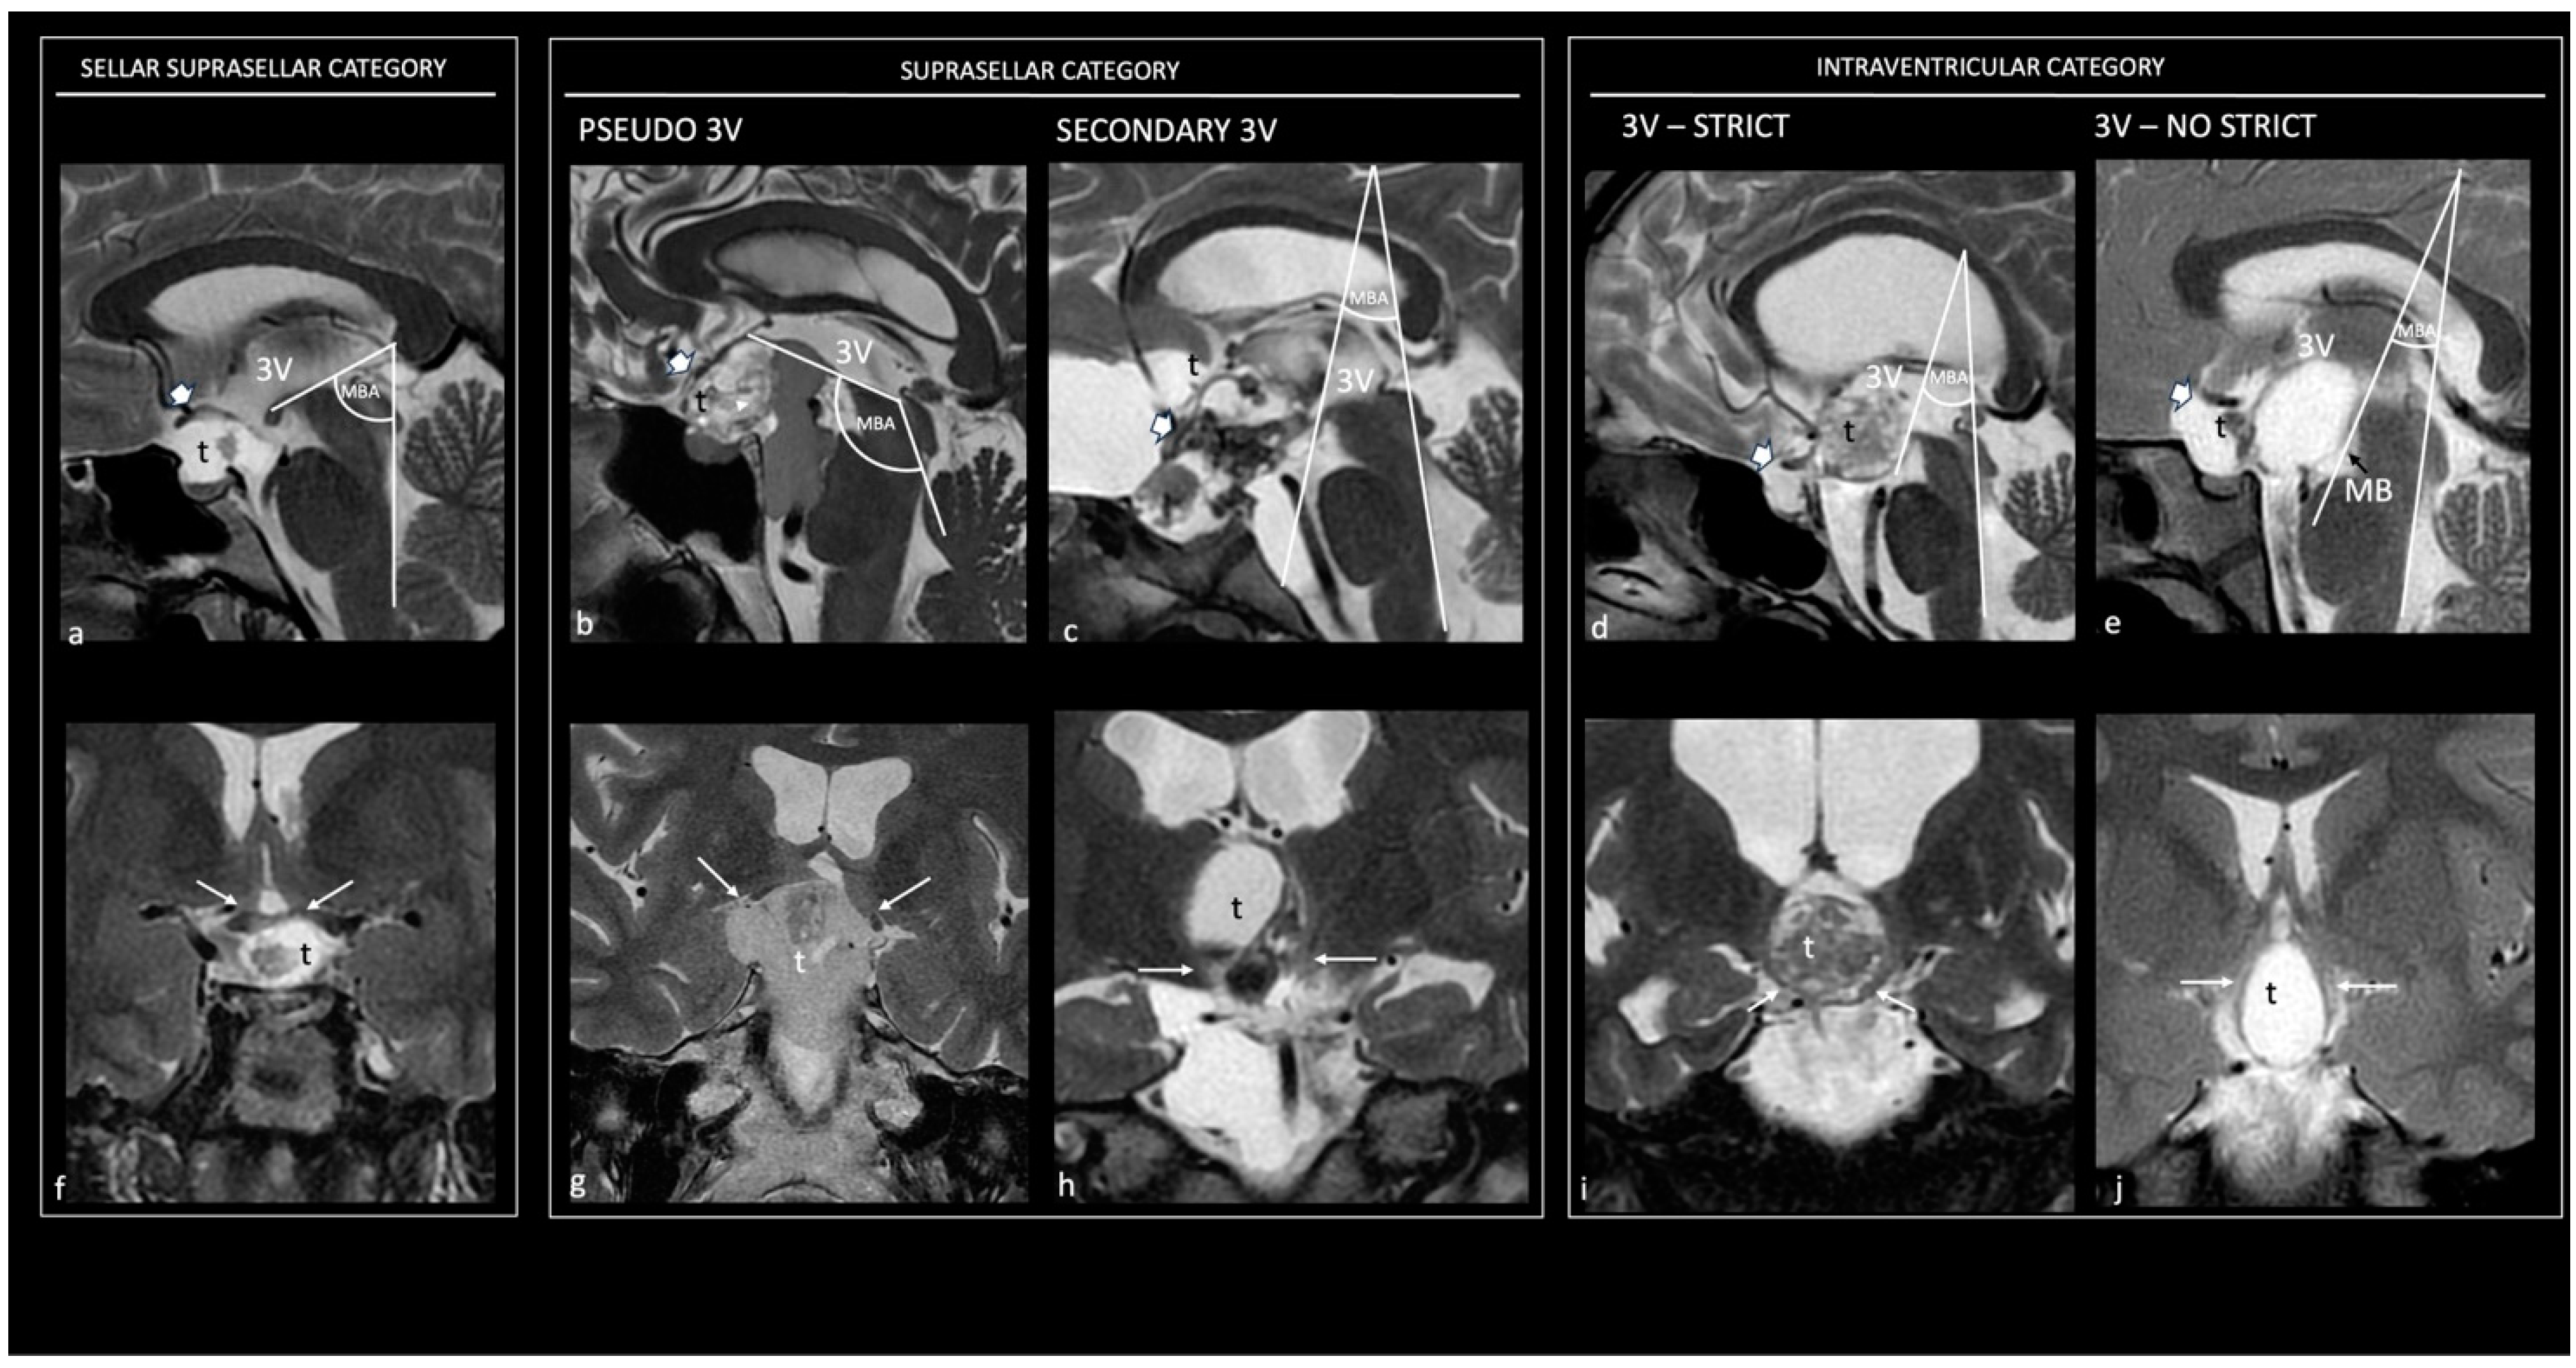

小児神経の画像診断 改訂第2版: ―脳脊髄から頭頸部・骨軟部まで。Neuroimaging Findings in a Patient with Anti-IgLON5 Disease。Topography and Radiological Variables as Ancillary。「小児神経の画像診断 = Diagnostic Imaging of Infantile Neurologic Diseases : 脳脊髄から頭頸部・骨軟部まで」大場 洋 / 大場 洋 / 髙梨 潤一 / 髙梨 潤一 / 森 墾 / 森 墾定価: ¥ 15000裁断しています。タイ方医学知識と理論。#大場洋 #大場_洋 #大場洋 #大場_洋 #髙梨潤一 #髙梨_潤一 #髙梨潤一 #髙梨_潤一 #森墾 #森_墾 #森墾 #森_墾 #本 #自然/医療・薬学・健康。健康教育マニュアル。書き込み等はありません。ページも全て揃ってページ順となってます。病理解剖実践ガイドブック 2025